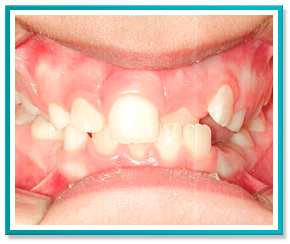

5. PROBLEMAS COM A DENTIÇÃO INFANTIL

Problemas com a dentição de seu filho?

Saiba que quanto antes for a intervenção, mais fácil, rápida e conservadora será a correção.

Veja a seguir as fotos de um caso onde foi necessário trazer para frente o incisivo central que encontrava-se totalmente escondido.

A correção foi feita através de aparelho removível com ação de molas, em menos de 1 ano de tratamento.